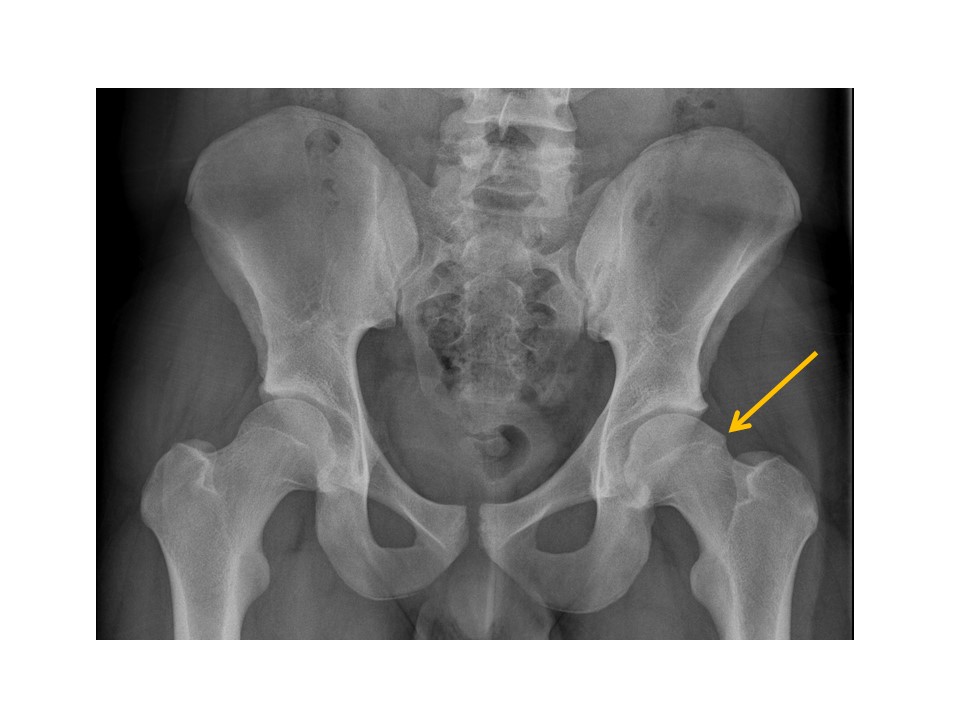

HIPS/PROXIMAL FEMURS

1. 1-Hip/pelvis fracture/malalignment as discussed above.